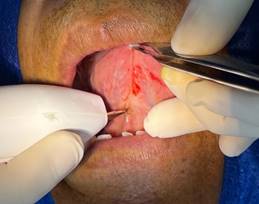

· Anestesia: Se realiza la anestesia infiltrativa regional y con un punto de punción del lado anestesiado se infiltra al otro lado del frenillo (contralateral). (Figura 3)

Figura 3. Técnica anestésica.

Elaboración: Los autores.